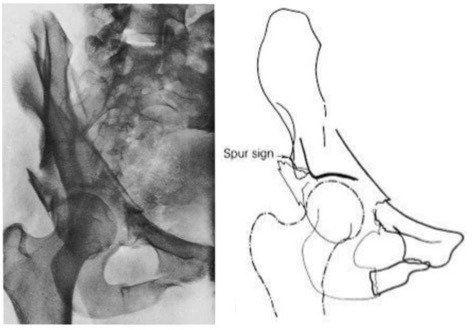

These anastamoses must be ligated as they appear on the lateral 13 of the superior pubic ramus. They are nearly universally present but vary significantly in size. Lateral femoral cutanous nerve l2 l3 nerve roots.

Thomas aquinas high school a roman catholic co educational college preparatory school has acquired national recognition for academic and athletic excellence. Posterior venous plexus injury in pelvic fractures can account for majority of blood loss. Corona mortis latin for crown of death is a common variant vascular anastomosis between the external iliac artery or deep inferior epigastric artery with the obturator arteryit is reported to be present in a third of patients on routine multi detector ct examination 14.

Laceration of corona mortis in 10 15. Knowledge of this variant vascular anastomosis is critical for surgical planning and in pelvic trauma as it is. 82 34954251 l 2 b select answer to see preferred response.